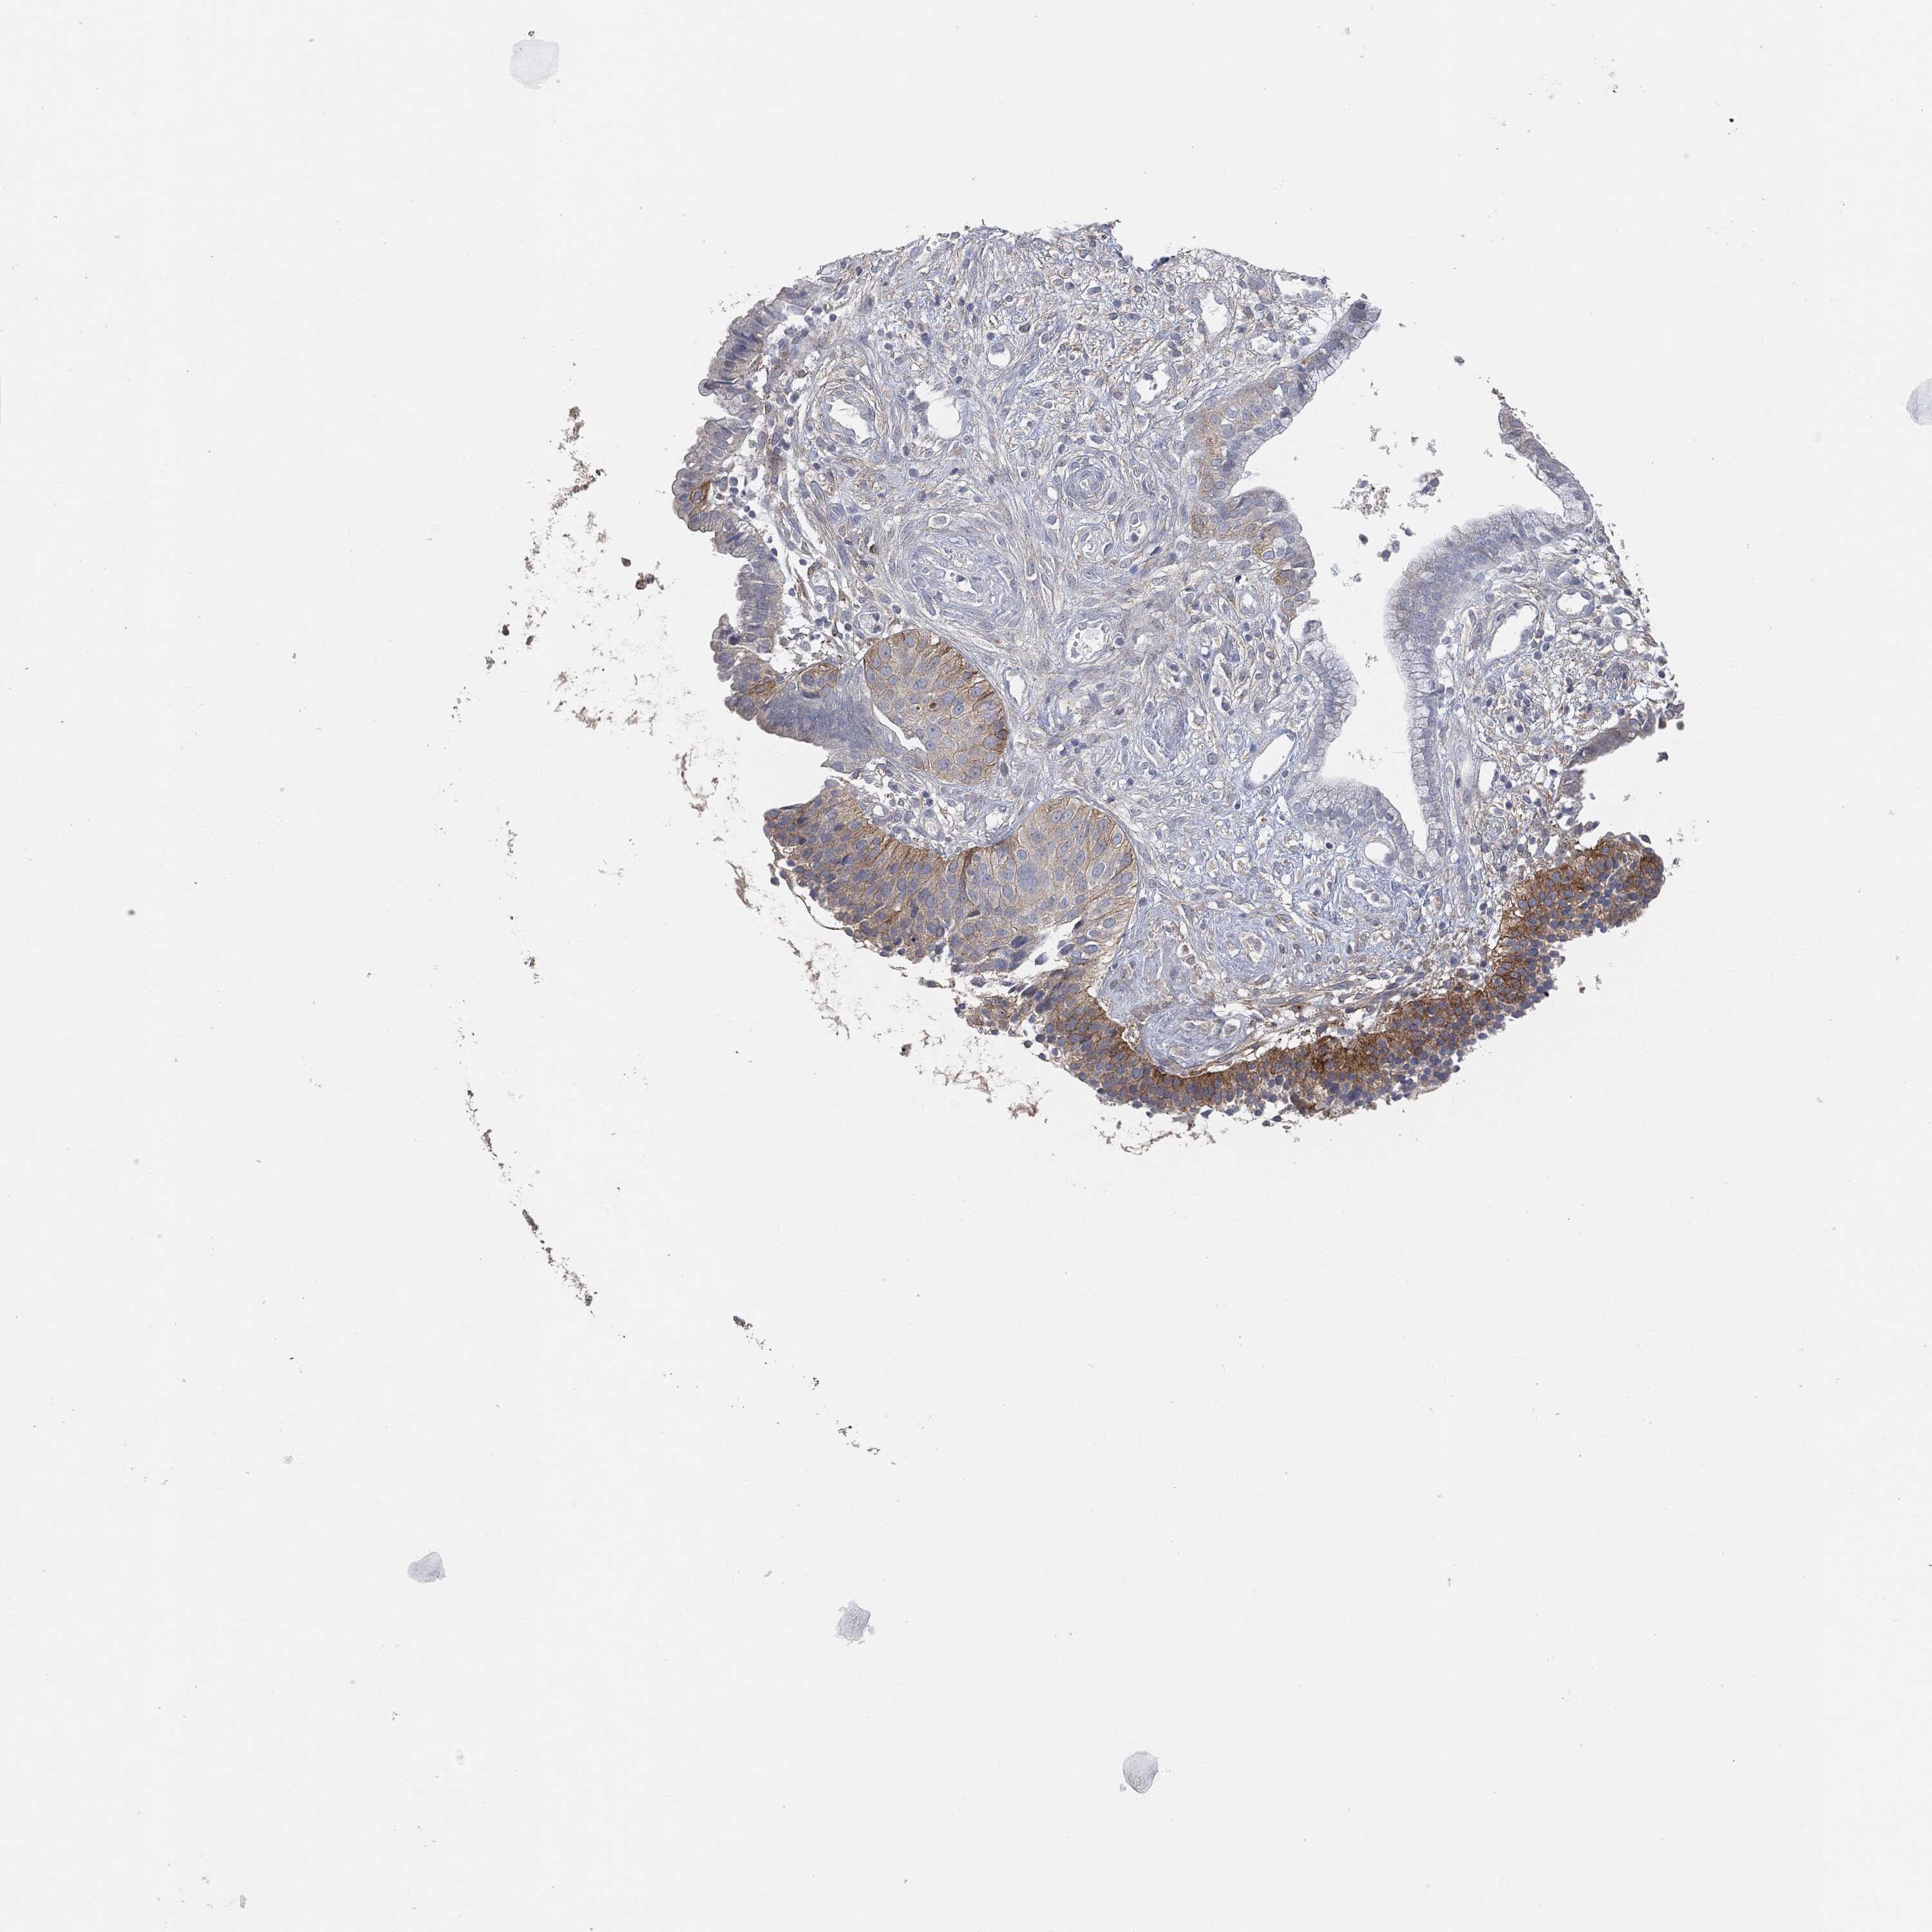

CERVICAL CANCER - Protein expressioni

A mouse-over function shows sample information and annotation data. Click on an image to view it in a full screen mode. Samples can be filtered based on level of antibody staining by selecting one or several of the following categories: high, medium, low and not detected. The assay and annotation is described here.

Note that samples used for immunohistochemistry by the Human Protein Atlas do not correspond to samples in the TCGA dataset.

Antibody stainingi

Antibody staining in the annotated cell types in the current human tissue is reported as not detected, low, medium, or high, based on conventional immunohistochemistry profiling in selected tissues. This score is based on the combination of the staining intensity and fraction of stained cells.

Each image is clickable and will lead to virtual microscopy that enables deeper exploration of all samples and also displays staining intensity scores, fraction scores and subcellular localization as well as patient and tissue information for each sample.

HPA001200

HPA018530

CAB000035

CAB068186

CAB073534

CAB080313

CAB080314

CAB080473

CAB080475

CAB080506

CAB080507

CAB080509

CAB080510

CAB080511

Staining

High

Medium

Low

Not detected

Intensity

Strong

Moderate

Weak

Negative

Quantity

>75%

75%-25%

<25%

None

Location

Nuclear

Cytoplasmic/membranous

Cytoplasmic/membranous,nuclear

Adenocarcinoma, NOS

Squamous cell carcinoma, NOS